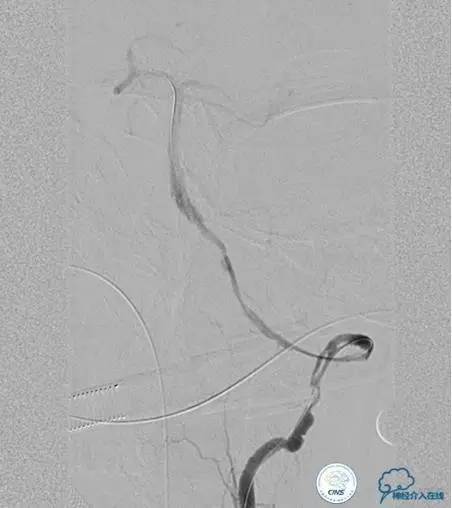

术前DSA

▼2013-12-13

▼2013-12-27

术后仍残余部分狭窄,但头晕明显缓解。

术后3个月复查时予行支架内球囊扩张,狭窄改善。